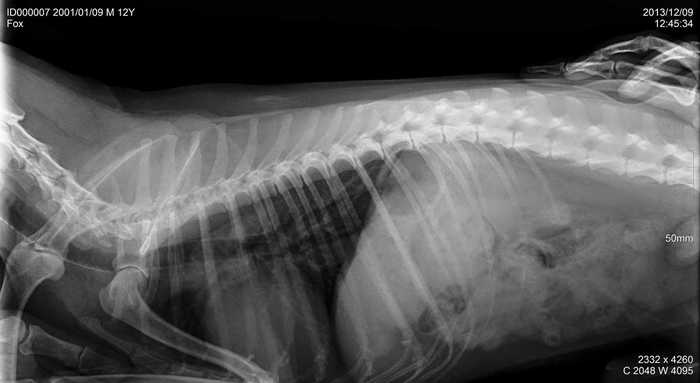

Úvod > Galerie > RTG snímky